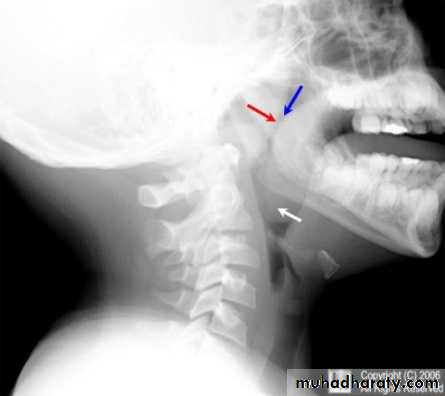

Adenoid facies

Investigations

X-ray of the postnasal space